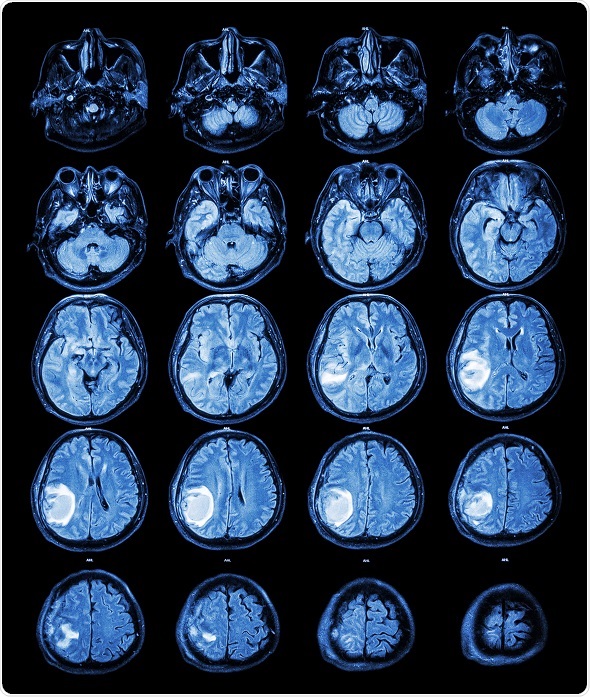

Image

Microscopic view of oligodendroglioma of the brain (right half blue) and normal brain (pink portion on the left). The brain cancer has invaded and replaced normal healthy brain tissue. Glioma of the brain. © vetpathologist / Shutterstock.com